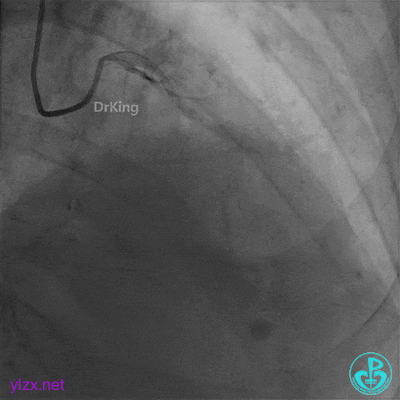

急诊冠脉造影

粗大前降支中段严重狭窄,血流3级。

粗大右冠脉中段严重狭窄,血流3级。